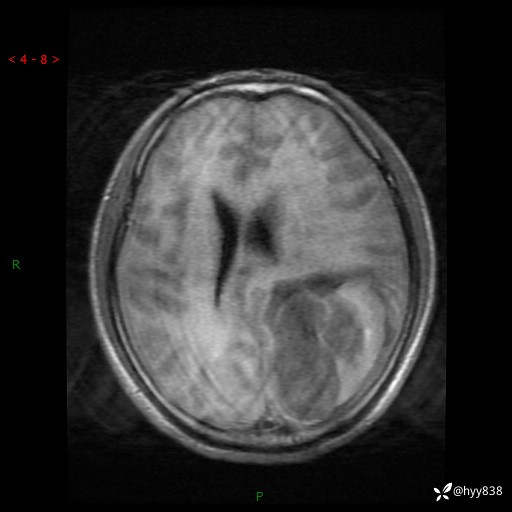

病例年轻小伙,头痛伴呕吐半年,渐进性加重1月。疑难病例,第一次见--结果公布~

性别:男

年龄:21岁

简要病史:头痛伴呕吐半年,渐进性加重1月

颅脑MRI平扫+增强